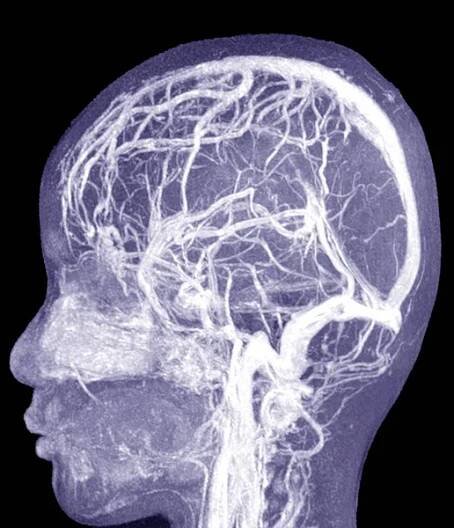

Otok mozku, edém mozku neboli mozkový edém je život ohrožující stav, který může být důsledkem úrazu hlavy, cévní mozkové příhody, infekce, hypoxie, nádoru mozku apod. Mozek je uzavřen v pevné lebce, která se samozřejmě nemůže rozšiřovat; otok mozku proto utlačuje krevní cévy, snižuje průtok krve…

Otok mozku (mozkový edém) je specifickým otokem části těla. Ostatní oteklé orgány či tkáně se mohou relativně volně zvětšit, mozek je však uzavřen v lebce, a proto je jeho otok spojen s nebezpečným zvýšením nitrolebního tlaku.

Co je to otok mozku?Otok mozku je stav, kdy mozková tkáň kvůli nahromaděné tekutině zvýší svůj objem. Intrakraniální tlak pak způsobuje zhoršení průtoku krve, což má za následek, že mozek není dostatečně okysličován. V důsledku tohoto stavu může dojít k poškození či odumření mozkových buněk.